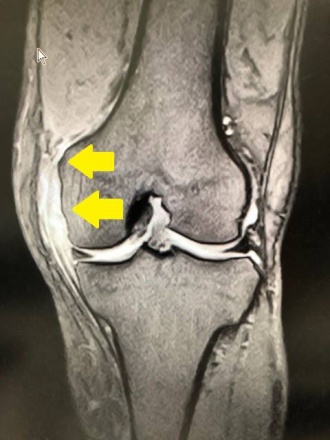

70歳代の男性が山で転んで左膝の怪我をして、当院を受診されました。膝の内側に強い痛みがあり、膝関節のMRI撮影を行いました。膝の内側の靭帯損傷(黄色矢印)で、内側側副靭帯損傷になります。

内側側副靭帯損傷は程度が軽い場合は、手術は必要なく通院で治療しています。